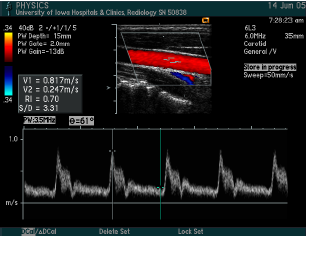

what measurements are taken?

what is calculated?

Common carotid artery

Internal carotid artery proximal

Internal carotid artery distal

External carotid artery

Vertebral

Subclavian

Peak systolic velocity, Peak end diastolic velocity

ICA/CCA ratio

what vessel is this waveform likely from?

CCA (below is distal CCA)